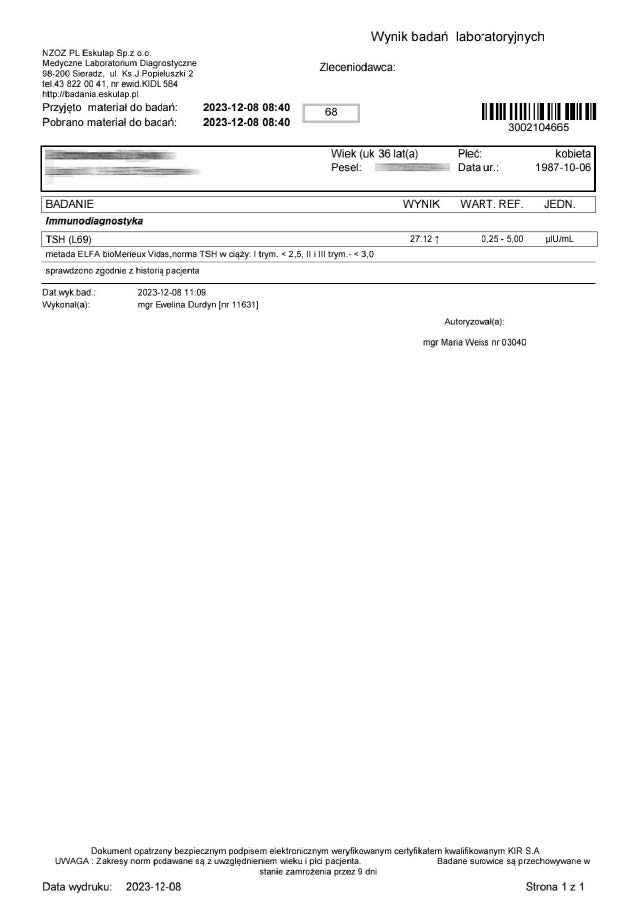

Kobieta lat 36 zastosowała terapię preparatem ze względu na pogarszające się samopoczucie i wysoki wynik TSH oraz anty-tpo jednoznacznie wskazujący na niedoczynność tarczycy. Brak zastosowanej farmakologii lewotyroksyną. Po zaledwie 12 dniach stosowania preparatu odnotowano znaczny spadek parametrów tarczycy oraz przeciwciał.

Wyniki odwrócenia procesów autoimmunologicznych wykraczają poza typowe leczenie i wykazują, że preparat wzmacnianjąc i stymulując mitochondria działa poprzez energetyczną optymalizację, co umożliwia długoterminową regenerację w różnych grupach wiekowych.